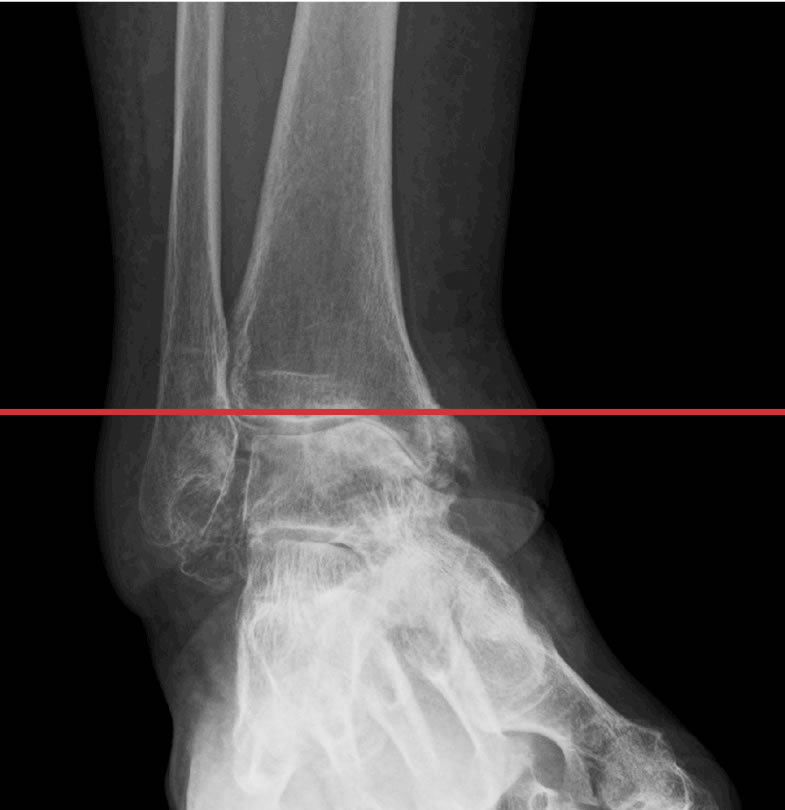

変形性足関節症

変形性足関節症の初期症状は、長時間歩行後の腫れや痛みや歩き始めの動かしづらさが主です。関節変形の進行とともに、凸凹面を歩く際の不安定感や早歩きや階段・坂の歩きにくさなどが出現し、痛みや腫れも起こりやすくなって立っているだけの時や安静時の痛みが起こることもあります。